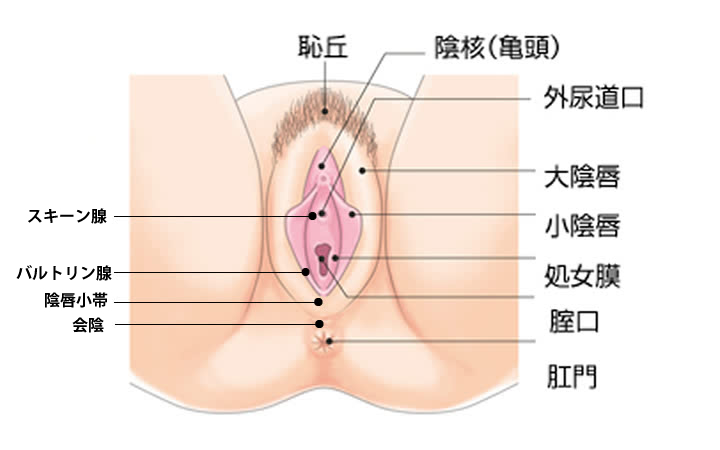

女性器について 正しい知識を持ちましょう ゆかりレディースクリニック 神戸市三宮にある婦人科

会陰 えいん は 腟口 ちつこう から肛門までを指します。 生殖器は発生学的由来により内生殖器と外生殖器に分けられます。外陰部は体表の皮膚が変化して生じた外生殖器で、外からの刺激に対して生殖器を守る役割があります。会陰部に近いほど男性化不全の程度が強い 4.陰嚢の形成は? 低形成、二分陰嚢の有無 <Quigley分類> 完全男性型 完全女性型 図:たのしく学ぶ小児内分泌より 外陰部の診察:女児の男性化 1.陰核の大きさは? 横径を計測することが多い。 >7 mm → 陰核肥大 2.膣口は確認できるか? 3.陰唇動画あり出張オイルリンパマッサージの四ツ目本舗は東京都心部のホテル・自宅へ、深夜1時迄、出張オイルリンパマッサージを提供。「no sokeibu, no life紙パンツを捨てよう!」当店の「鼠径部(そけい部)オイルリンパマッサージ」の「会陰部について」の説明

女性器について 正しい知識を持ちましょう ゆかりレディースクリニック 神戸市三宮にある婦人科